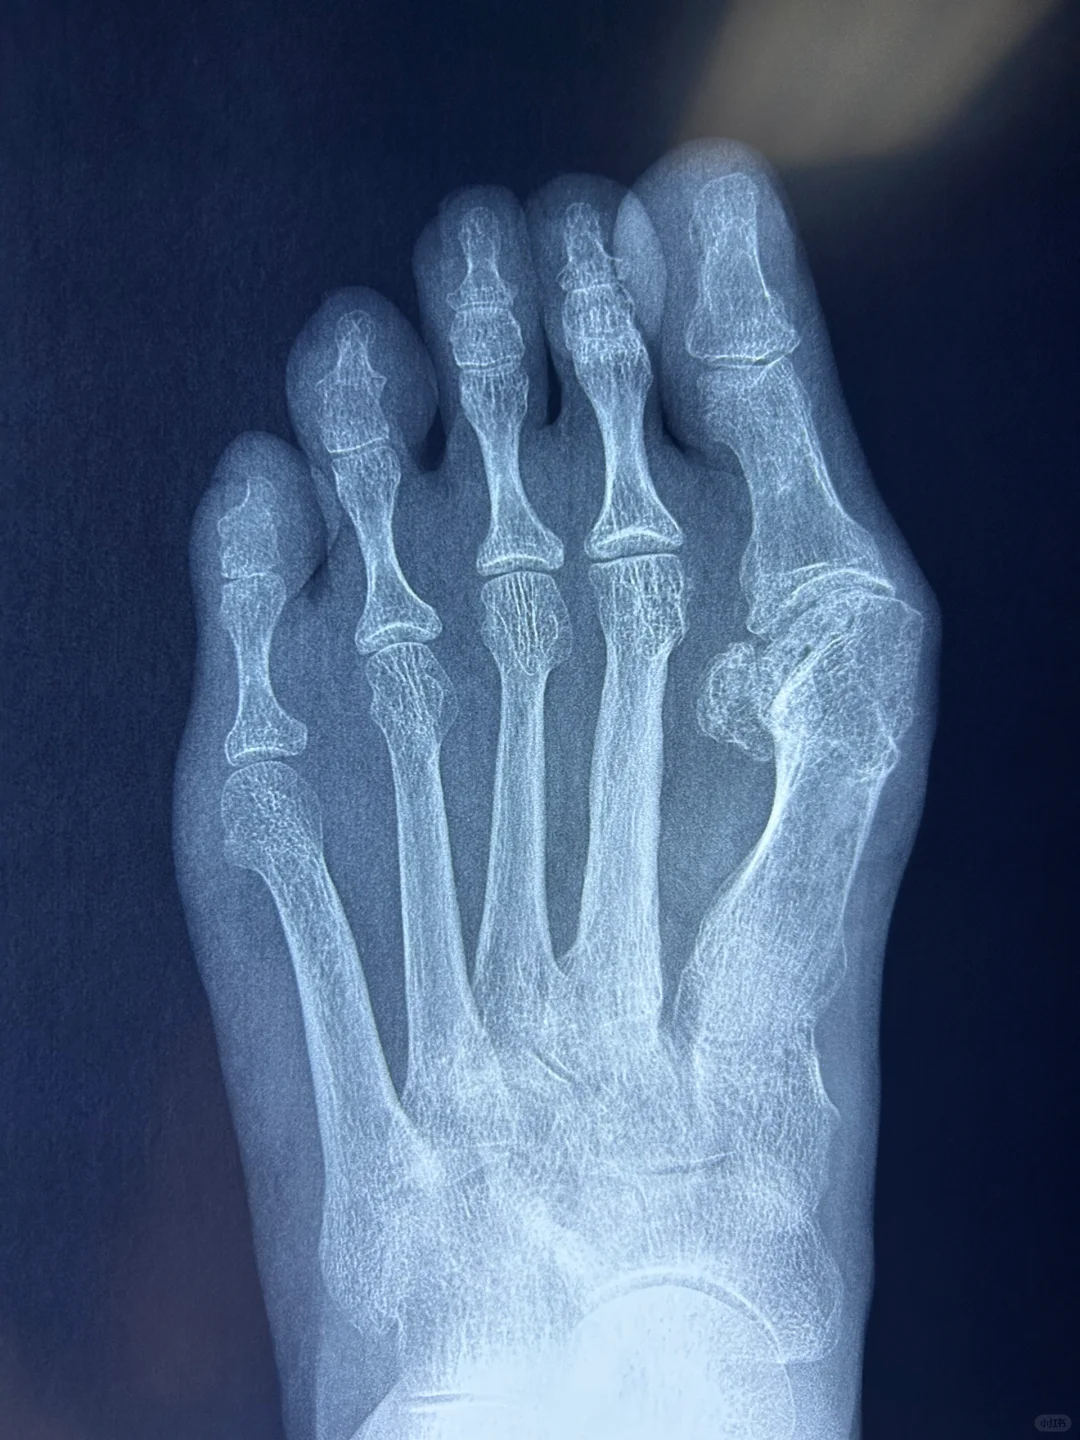

拇外翻术后X片